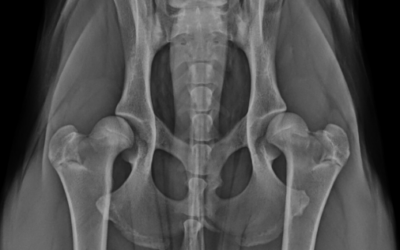

Tibial Plateau Leveling Osteotomy (TPLO)

Cruciate ligament disease is one of the most common causes of hindlimb lameness in dogs.